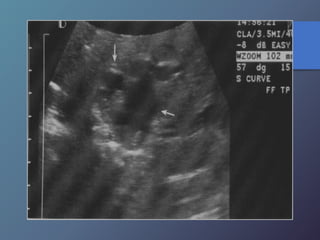

Cirrosis Hepática

Proceso difuso hepático caracterizado

por fibrosis y la conversión de la

arquitectura normal del hígado en

nódulos estructuralmente anormales.

• Redistribución de volumen. Índice

caudado/lob. Der. 0.65.

• Ecoestructura grosera.

• Superficie nodular.

• Nódulos de regeneración.

• Nódulos displásicos.

• Hipertensión portal: Ascitis, esple-

nomegalia, varices.

Características Ecográficas

• Redistribución devolumen. Índice caudado/lob. Der. 0.65. • Ecoestructura grosera. • Superficie nodular. • Nódulos de regeneración. • Nódulos displásicos. • Hipertensión portal: Ascitis, esple- nomegalia, varices. Características Ecográficas Cirrosis Hepática